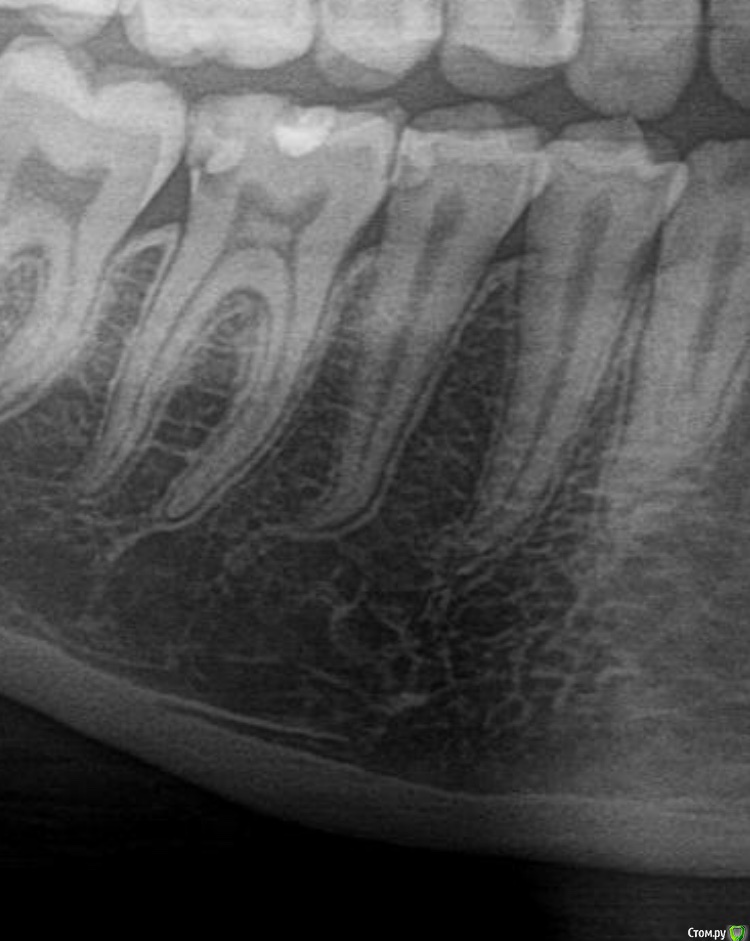

Marialalala Опубликовано 22 марта, 2020 Поделиться Опубликовано 22 марта, 2020 (изменено) Месяц назад лечила за один приём средний (по словам врача и чеку) кариес в двух нижних зубах (6 и 5). К врачу этому попала случайно, не мой постоянный врач. На днях сделала панораму для дальнейшего лечения зубов и вот такая картина. Позвонила тому врачу он сказал - что все ок, это так выглядит не рентгеноконтрастная изолирующая прокладка под пломбой. Скажите - это действительно так или всё-таки это просто плохо пролеченный кариес (лечили сбоку шестой к седьмому и также пятый сбоку к шестому). Фото зуба после лечения и до лечения кариеса прикрепляю Изменено 22 марта, 2020 пользователем Marialalala Ссылка на комментарий

Zlata-doctor Опубликовано 23 марта, 2020 Поделиться Опубликовано 23 марта, 2020 Мое мнение. Кариес глубокий, требует незамедлительного лечения ( не прямо сегодня, но по возможности, в ближайшее время). В шестом обширная кариозная полость на дистальной поверхности ( та, что прилегает к 7) и на менее общирная на медиальной ( которая прилегает к 5), на 5 полость дистальной поверхности. К слову сказать, при среднем кариесе никаких изолирующих прокладок не требуется. Я бы, как доктор, сделала прицельный снимок 5,6 зуба, может быть, в разных проекциях, для уточнения диагноза. Хороший прогноз у этих зубов есть ( сделать качественную реставрацию с сохранением витальности зубов), если вы попадете в хорошие руки. 1 Ссылка на комментарий